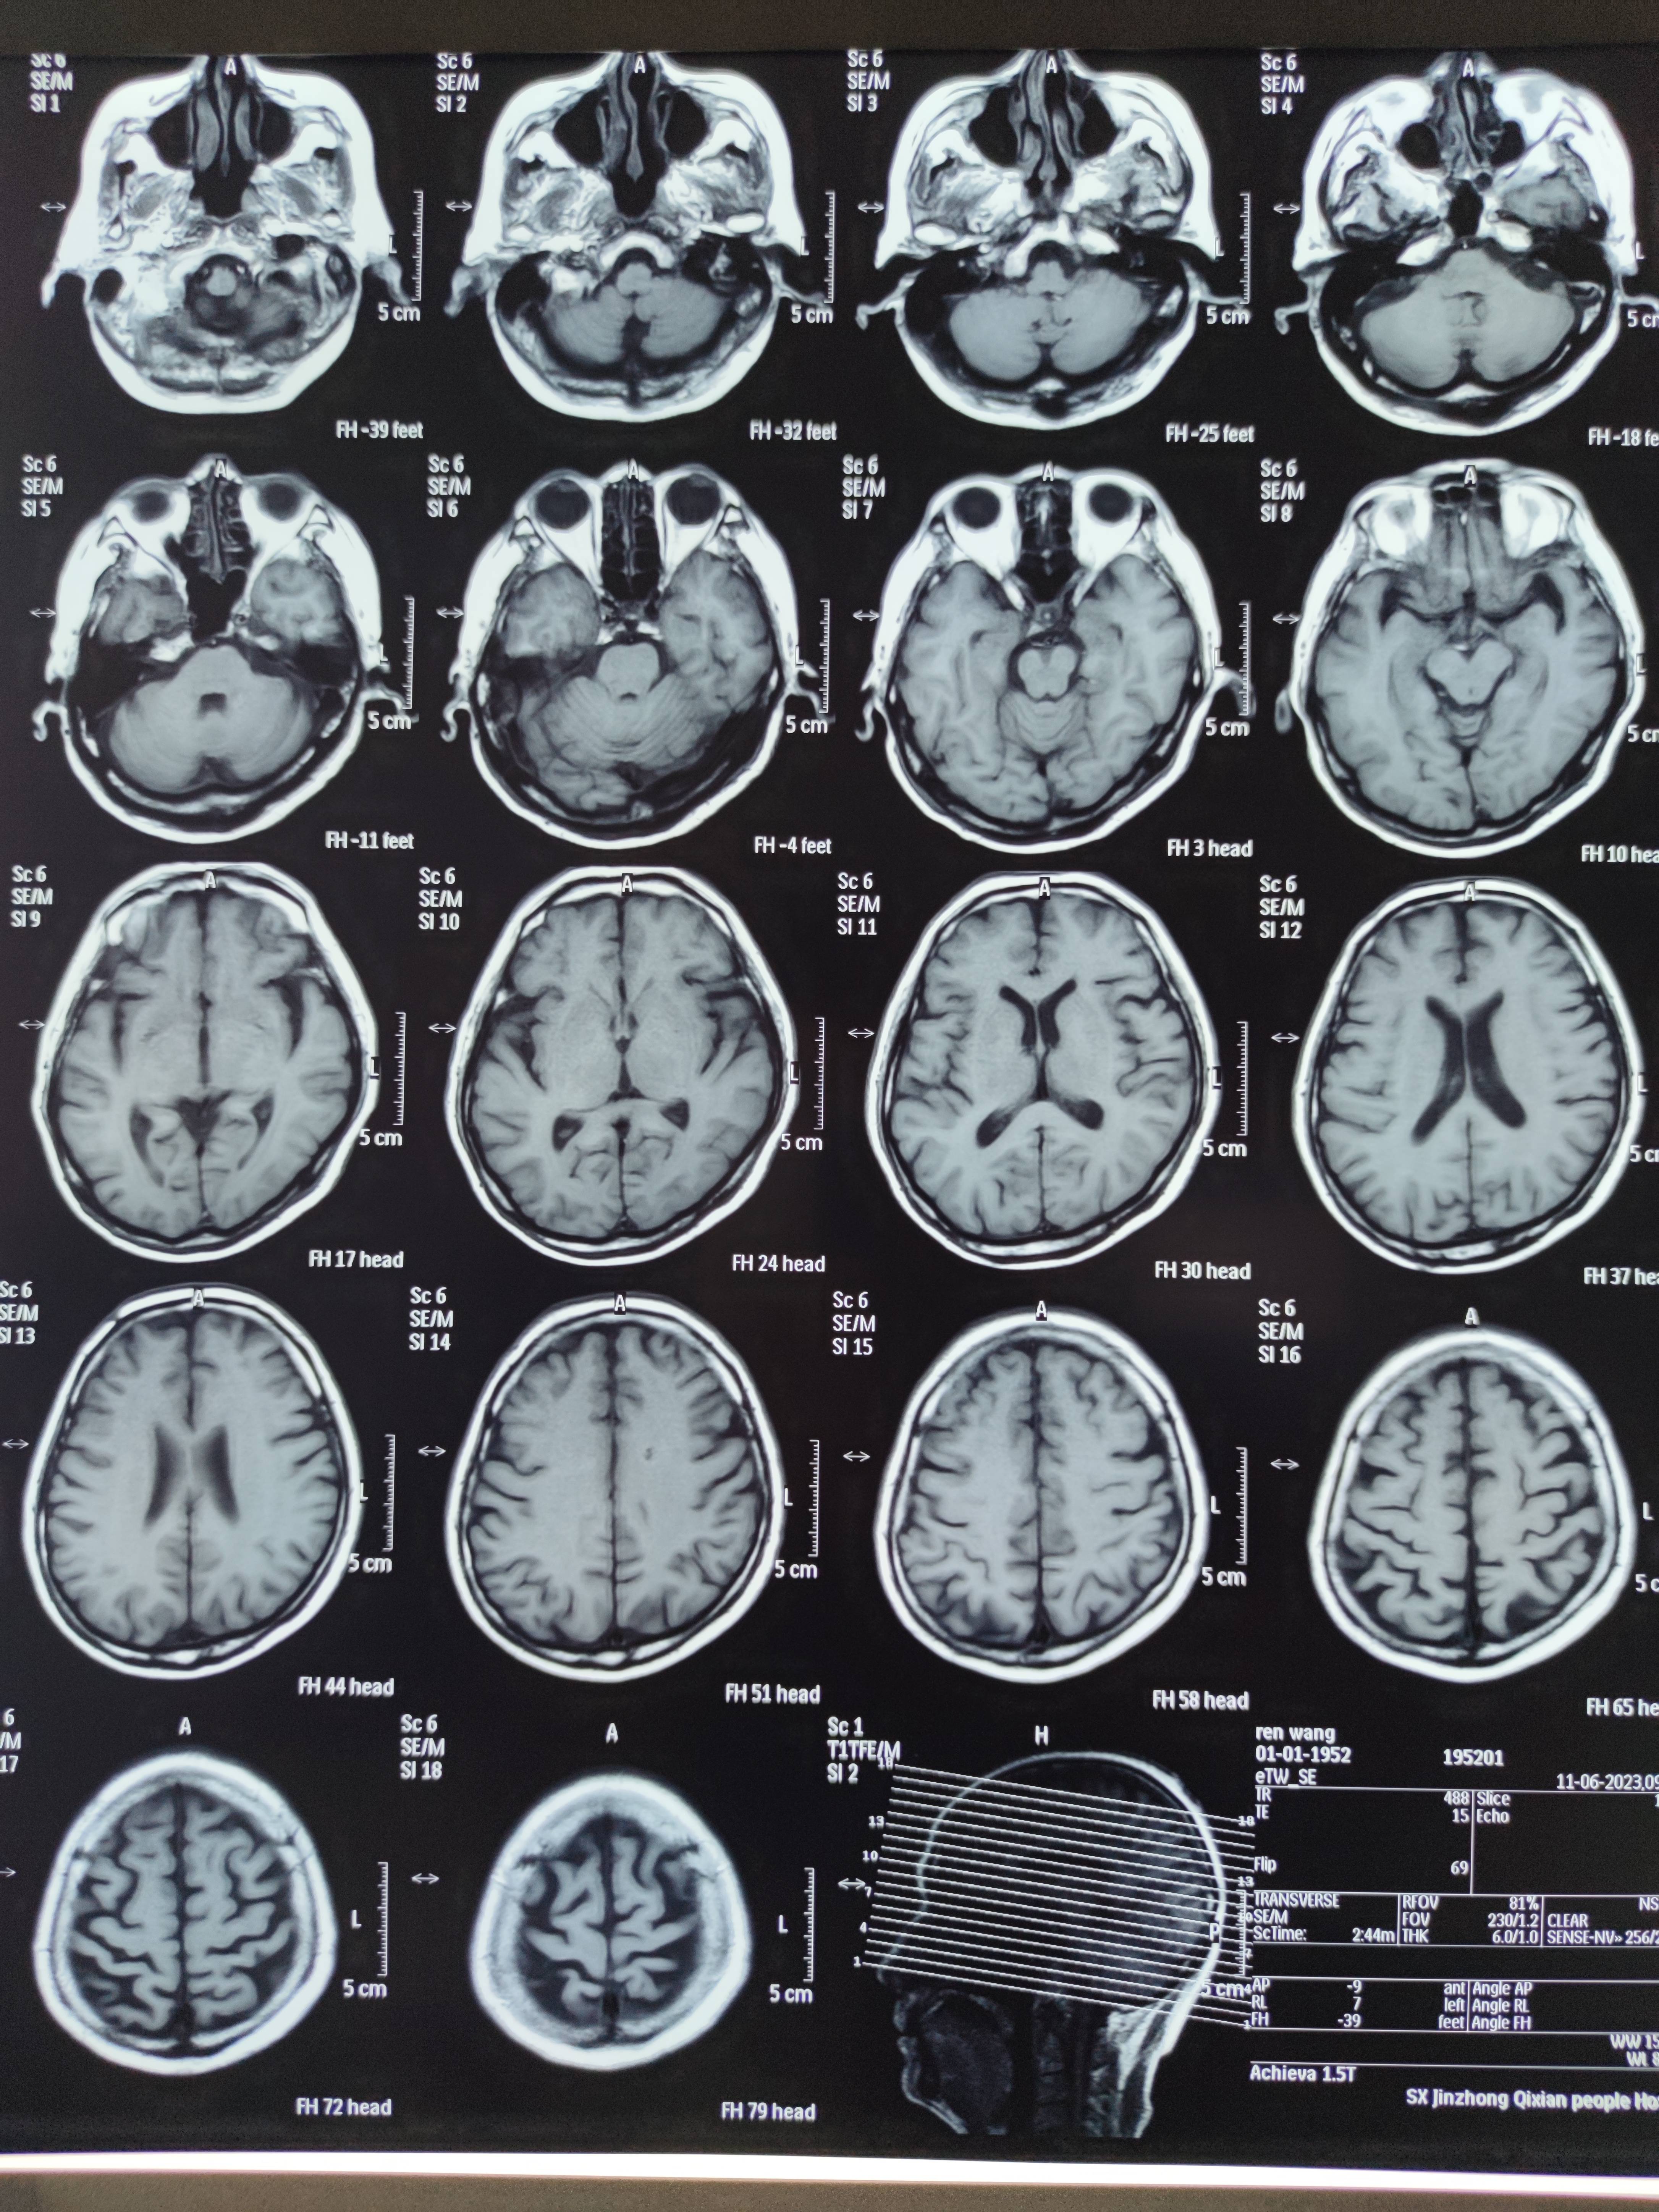

四月份癌胚抗原还是5.6,这个月到8了,持续升高。做了核磁增强,左侧桥小脑角哪有个地方不确定。肝脏核磁平扫弥散有两个点状高信号,转移也排不了,胃肠镜正常,左颈部有个变圆的淋巴结,保险点是不该加个化疗药了?咨询了陈波主任,等结果的吧!图片